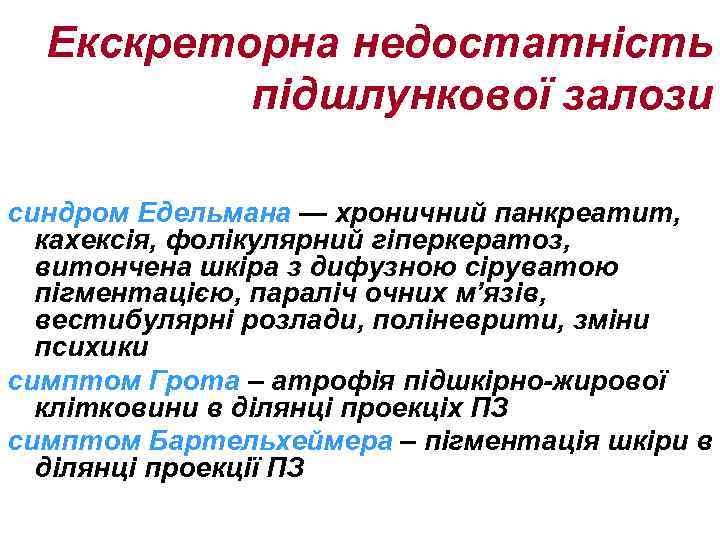

Екскреторна недостатність підшлункової залози синдром Едельмана — хроничний панкреатит, кахексія, фолікулярний гіперкератоз, витончена шкіра з дифузною сіруватою пігментацією, параліч очних м’язів, вестибулярні розлади, поліневрити, зміни психики симптом Грота – атрофія підшкірно-жирової клітковини в ділянці проекціх ПЗ симптом Бартельхеймера – пігментація шкіри в ділянці проекції ПЗ

Екскреторна недостатність підшлункової залози синдром Едельмана — хроничний панкреатит, кахексія, фолікулярний гіперкератоз, витончена шкіра з дифузною сіруватою пігментацією, параліч очних м’язів, вестибулярні розлади, поліневрити, зміни психики симптом Грота – атрофія підшкірно-жирової клітковини в ділянці проекціх ПЗ симптом Бартельхеймера – пігментація шкіри в ділянці проекції ПЗ